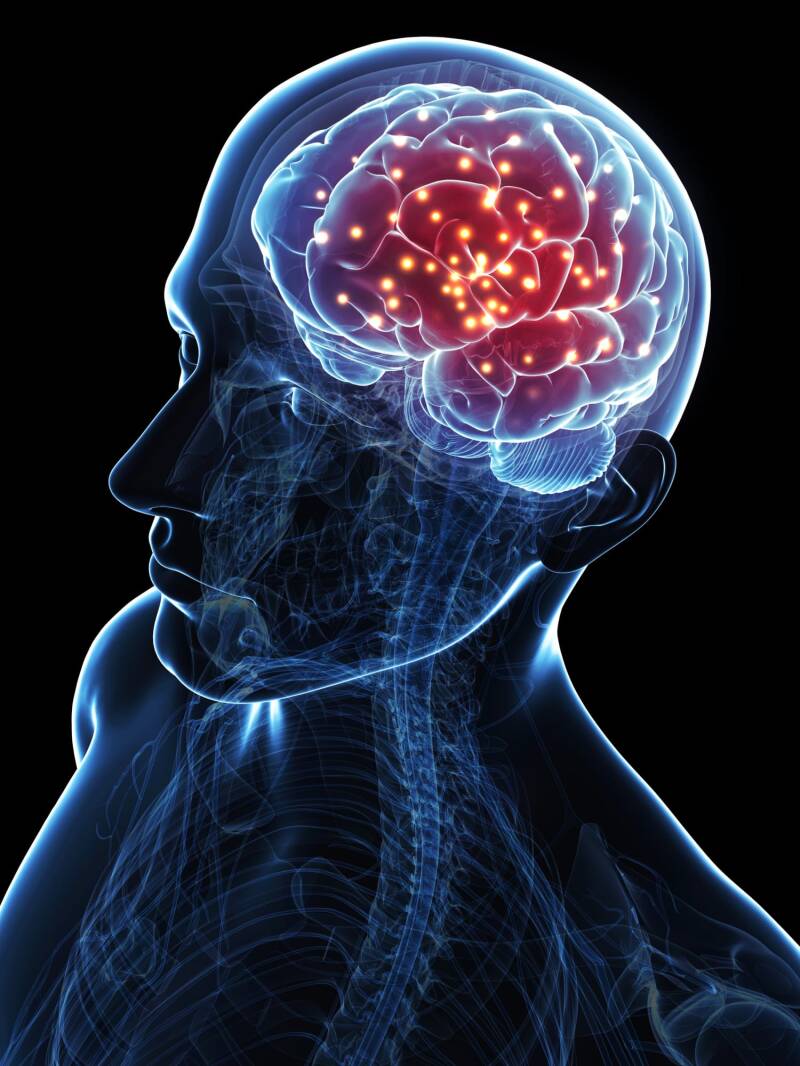

8- There are 100 billion neurons present in the brain.